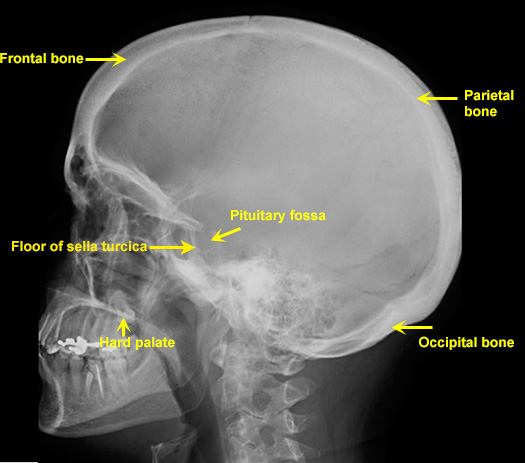

Plain Films of Skull and Spine